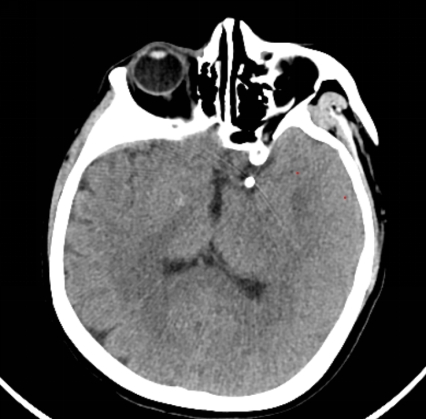

许刚副主任在仔细研究过患者的病历及影像资料后,建议患者早期行手术治疗,给出了患者三个治疗方案,开颅夹闭手术,常规弹簧圈加支架介入栓塞手术,而最后一种,则是目前最先进的方式WEB™植入术。经过详细告知和沟通,患者家属最终选择了行WEB™植入手术。于是在充分完善术前准备后,在影像介入室、麻醉科以及屈满莉护师的全力配合下,许刚副主任、张明副主任医师在全麻下为患者施行了大脑中动脉瘤内扰流装置WEB植入术,因为有之前的手术经验,手术过程十分顺利,仅用时15分钟就完成了WEB植入,术中即刻造影显示动脉瘤内造影剂滞留明显,其余左侧大脑中动脉、大脑前动脉等血管均通畅。患者术后顺利苏醒,拔管后未诉特殊不适,言语功能及肢体功能均未受影响。2天后患者出院。

术后CT